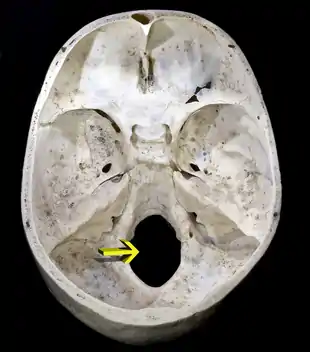

Partie droite de la base du crâne humain.